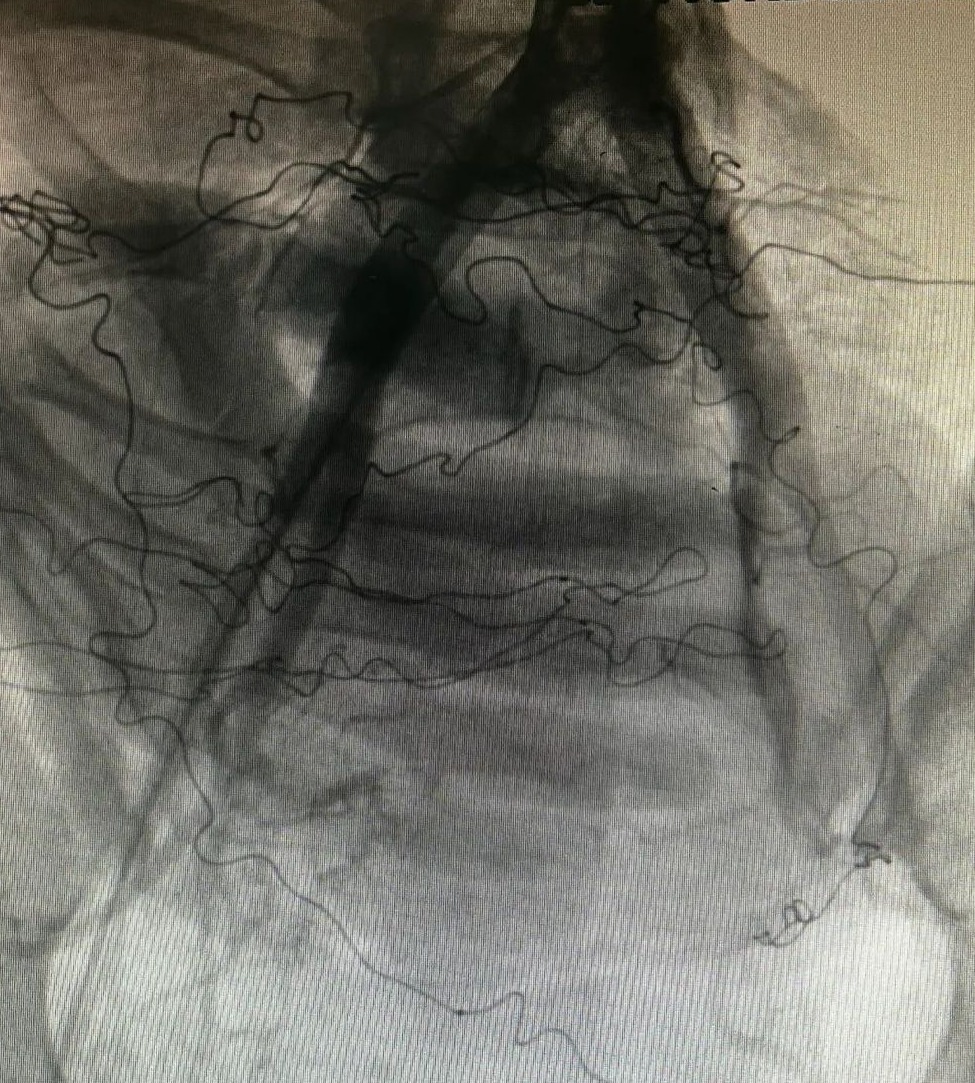

▲杨永久(左)在介入手术中

那一晚,我接到妇产科抢救的电话后,就立即赶到医院了。到达手术室后,我看到辛主任带领团队正在紧张抢救。浸满血液的纱布堆得像小山一样。显然产妇的情况已经十分危险了。我赶紧同我们科的值班二线丁旭一起,为产妇进行动脉介入止血。手术过程中,产妇子宫用温热盐水纱垫湿敷加压止血,当我们成功阻断了动脉血之后,妇产科团队再次进行药物促宫缩,凌晨1:00,产妇的子宫收缩明显好转,无明显出血点,在为产妇留置引流管后顺利关腹,抢救宣告成功!

▲术中影像资料:辛德梅的手影清晰可见